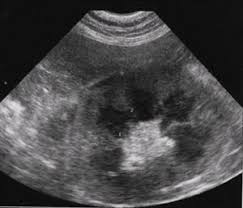

Renal lymphoma is lymphoma in the kidneys and is one of the worst forms of lymphoma for a cat to contend with. Lymphomas are the most commonly there is no true treatment for renal lymphoma in cats. The case shows that treating renal lymphoma in cats by adequate combination chemotherapy can achieve long survival times with a good quality of life. Poor appetite, excessive water consumption, weight loss, possibly vomiting. Learn more about when to see a doctor. Bilaterally enlarged, and sometimes irregular, kidneys can be found on palpation of the abdomen and confirmed radiographically. It is one of several forms of feline lymphomas. Feline renal lymphoma involves the renal or kidney region in cats.

Bilaterally enlarged, and sometimes irregular, kidneys can be found on palpation of the abdomen and confirmed radiographically.